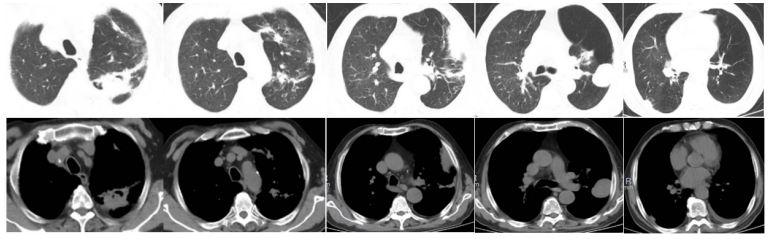

2023年5月26日NGS回报毛霉,经过讨论,建议艾沙康唑、两性霉素B雾化+静脉滴注、奥马环素200 mg ivd首剂,100 mg qd治疗。艾沙康唑200 mg qd+两性霉素B静滴(5月26日两性霉素B胆固醇硫酸酯复合物100 mg qd,5月27日换用两性霉素B脂质体150 mg→250 mg→350 mg qd)+两性霉素B 12.5 mg bid雾化+奥马环素100 mg qd(200 mg ivd首剂)。2023年6月5日复查胸部CT:弥漫性病变明显吸收,左上肺病灶明显呈现机化限制,病灶体积没有扩大;左肺出现新的实变影(图4)。从病灶性质上看,似乎是机化的过程,加之患者临床症状明显改善,经过讨论认为该方案是有效的,所以继续使用该治疗方案。慢性阻塞性肺疾病伴急性加重;肺真菌病(曲霉、毛霉);呼吸衰竭;糖尿病;高血压;低蛋白血症;低钾血症;颈椎术后(脊髓型颈椎病);腰椎间盘突出。①奥玛环素片300 mg/片,每日一次。②两性霉素B每日两次,每次25 mg雾化吸入。2~3月后改每天雾化一次,一次半支(12.5 mg)。③艾沙康唑20 0mg qd,维持30 min。④两性霉素B脂质体350 mg qd 60 min以上滴完。易低钾,注意监测血钾。2023年6月25日出院后复查胸部CT:病灶基本吸收,左下叶出现新病灶,边缘光滑,考虑原有肺大泡内充填了一些渗出性病变(图5)。但并未将其定义为一个新的病变,因为它不像典型的曲霉或毛霉感染的新发病变特征,并且患者症状非常逍遥,所以仍沿用原方案继续治疗。

2023年7月21日胸部CT可见病灶较前进一步吸收(图6),停两性霉素B脂质体,艾沙康唑由静脉序贯为口服,两性霉素B雾化qd。

2023年10月10日随访胸部CT病灶仍在继续吸收(图7)。艾沙康唑口服两性霉素B雾化qd。11月13日胸部CT示左下肺病灶基本稳定(图8)。